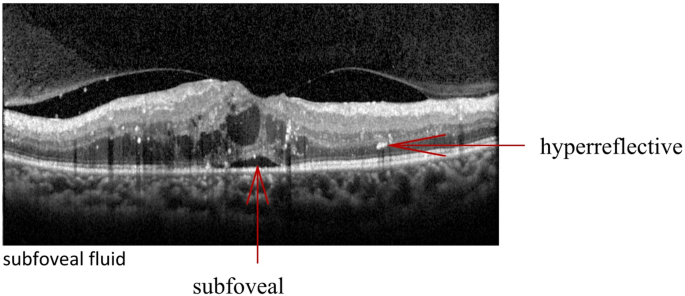

OCT images were acquired using 6-mm vertical and horizontal scans centered on the fovea in high-resolution mode with spectral domain OCT (SD-OCT, Heidelberg Spectralis OCT, Heidelberg Engineering, Germany). Recorded quantitative variables included (1) central macular thickness (CMT) and (2) the total number of hyperreflective foci (HRF) across retinal layers. Qualitative parameters were assessed for (1) size of intraretinal cysts (IRC), (2) integrity of the ELM and EZ, (3) presence of disorganization of the inner retinal layers (DRIL), and (4) presence of subfoveal fluid (SRF). All the subjects underwent examinations twice. All OCT images were analysed by the blinded retina specialist(Li-na Lv) and averages were determined. According to the TCED-HFV grading system (Table 1), the DME was divided into early, advanced, severe, and atrophic stages10 (Table 2, represented in Figs. 1, 2, 3 and 4).

Advanced DME Intermediate cystoid spaces in the fovea. The EZ is not gradable, but the ELM is disrupted subfoveally. The segmentation of the internal retinal layers is still visible. The presentation of vitreous macular traction is obvious. The TCED-HFV grading is T = 2, C = 2, E = 1, D = 1, H = 1, F = 1, and V = 3.